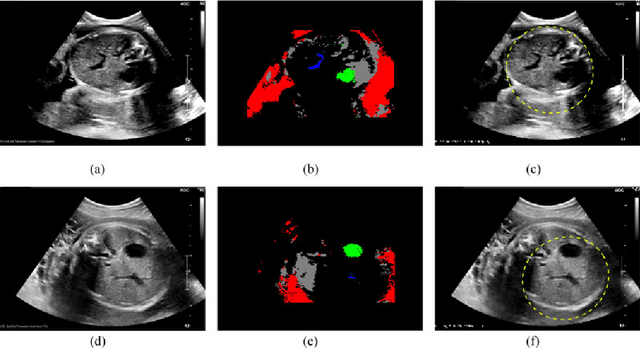

Abstract:Ultrasound diagnosis is routinely used in obstetrics and gynecology for fetal biometry, and owing to its time-consuming process, there has been a great demand for automatic estimation. However, the automated analysis of ultrasound images is complicated because they are patient-specific, operator-dependent, and machine-specific. Among various types of fetal biometry, the accurate estimation of abdominal circumference (AC) is especially difficult to perform automatically because the abdomen has low contrast against surroundings, non-uniform contrast, and irregular shape compared to other parameters.We propose a method for the automatic estimation of the fetal AC from 2D ultrasound data through a specially designed convolutional neural network (CNN), which takes account of doctors' decision process, anatomical structure, and the characteristics of the ultrasound image. The proposed method uses CNN to classify ultrasound images (stomach bubble, amniotic fluid, and umbilical vein) and Hough transformation for measuring AC. We test the proposed method using clinical ultrasound data acquired from 56 pregnant women. Experimental results show that, with relatively small training samples, the proposed CNN provides sufficient classification results for AC estimation through the Hough transformation. The proposed method automatically estimates AC from ultrasound images. The method is quantitatively evaluated, and shows stable performance in most cases and even for ultrasound images deteriorated by shadowing artifacts. As a result of experiments for our acceptance check, the accuracies are 0.809 and 0.771 with the expert 1 and expert 2, respectively, while the accuracy between the two experts is 0.905. However, for cases of oversized fetus, when the amniotic fluid is not observed or the abdominal area is distorted, it could not correctly estimate AC.